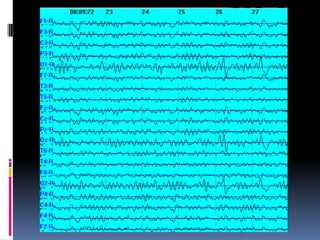

 El patron-EEG caracteristico es la hipsarritmia

que primero aparece en sueño y luego en

vigilia

 Consiste en ondas difusas de alto voltaje

(>400 mV) con una actividad de base caotica,

puntas multifocales, ondas agudas y muy

poca sincronia entre los hemisferios.

 Los espasmos se asocian a los

electrodecrementos

Síndrome de West El patron-EEG caracteristico es la hipsarritmia que primero aparece en sueño y luego en vigilia  Consiste en ondas difusas de alto voltaje (>400 mV) con una actividad de base caotica, puntas multifocales, ondas agudas y muy poca sincronia entre los hemisferios.  Los espasmos se asocian a los electrodecrementos